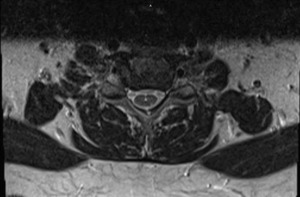

A second MRI examination of the cervical spine without contrast was ordered approximately 1 year following the accident due to persistent and worsening symptoms. This was necessary to evaluate radiculopathy and to rule out enlargement of syringohydromyelia. The syringohydromyelia at the cervical and upper thoracic cord was unchanged compared to a study 6 months prior. Annular tear, mild posterior disc bulging and mild disc degeneration were present at C3-C4. Mild bulging and degeneration was present at the C5-C6 disc with Luschka joint osteophytes and severe foraminal stenosis at C6 on the right. Severe disc degeneration was evident at C6-C7 with mild disc bulging and severe bilateral bony foraminal stenosis at C7. There was no evidence of Chiari malformation, tumor, or other congenital anomalies. (See Figures 1-4)

She was diagnosed with traumatically-induced cervical radiculopathy, cervical spine segmental dysfunction, and syringohydromyelia at the cervical and upper thoracic cord. Pre-existing disc degeneration and osteophytes at the cervical spine may have predisposed her to this condition.